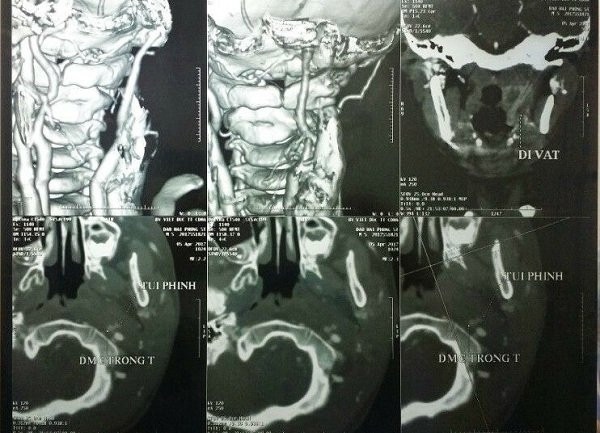

Chụp mạch cảnh xóa nền dựng hình 3D xác định vị trí của dị vật.

Sau đó, chúng tôi đã cùng hội chẩn với chuyên gia chẩn đoán hình ảnh là ThS.BS Lê Văn Khảng của Bệnh viện Bạch Mai. Với những nỗ lực cùng kinh nghiệm của mình, ThS. Khảng đã phát hiện hình ảnh dị vật đứt làm 2 đoạn, đâm vào nền sọ làm rách động mạch cảnh trong.

Đến giai đoạn này là phần của chuyên gia mạch máu, BS. Lư đã phải rất thận trọng, khéo léo, tỉ mỉ vừa cầm máu, buộc mạch và bóc tách để lấy dị vật, cuối cùng đã lấy ra được hai dị vật có chiều dài 1cm và gần 5cm. Lúc này cả ekip mới thở phào nhẹ nhõm”.